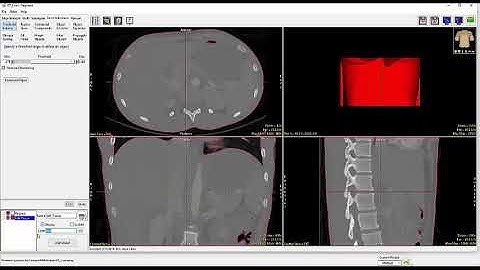

Analyze 14.0 - Segment: Multiple CT Object Segmentation using Object Extractor